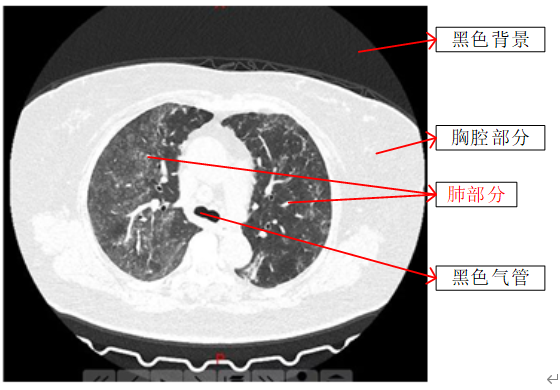

根据对已有的图片分析,得到图片的各个部分如下图2所示:

为了将肺部区域分割出来,要进行如下的操作: